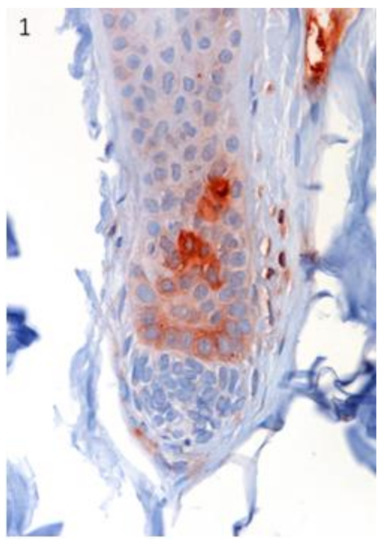

3.1. Stem Cell Marker Analyses in Healthy Skin. Sox9 and Lgr5 Protein Expression was Confirmed in Specific Regions of Canine Hair Follicle